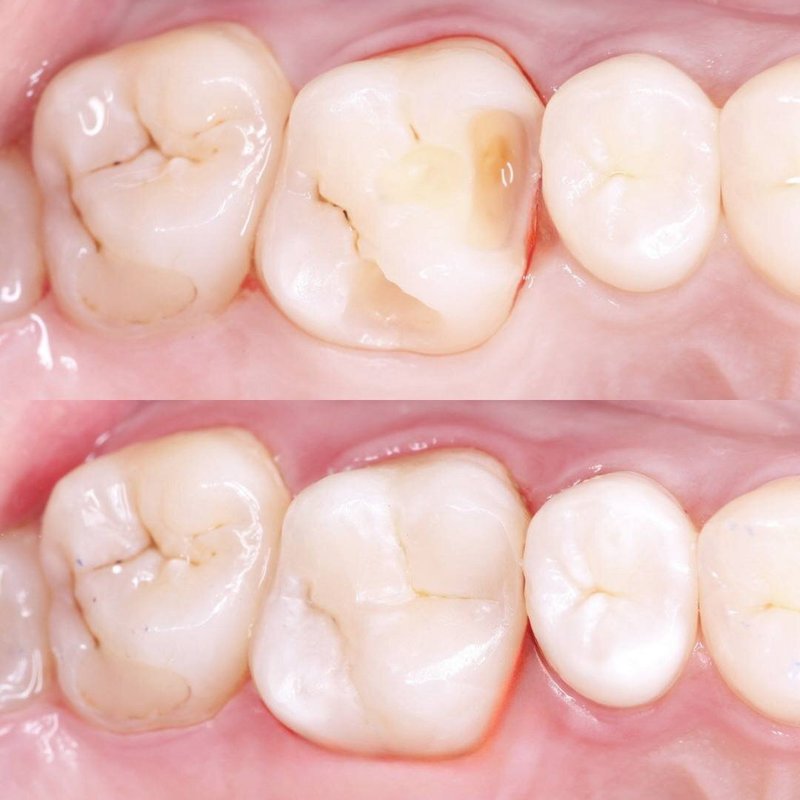

Фотогалерея